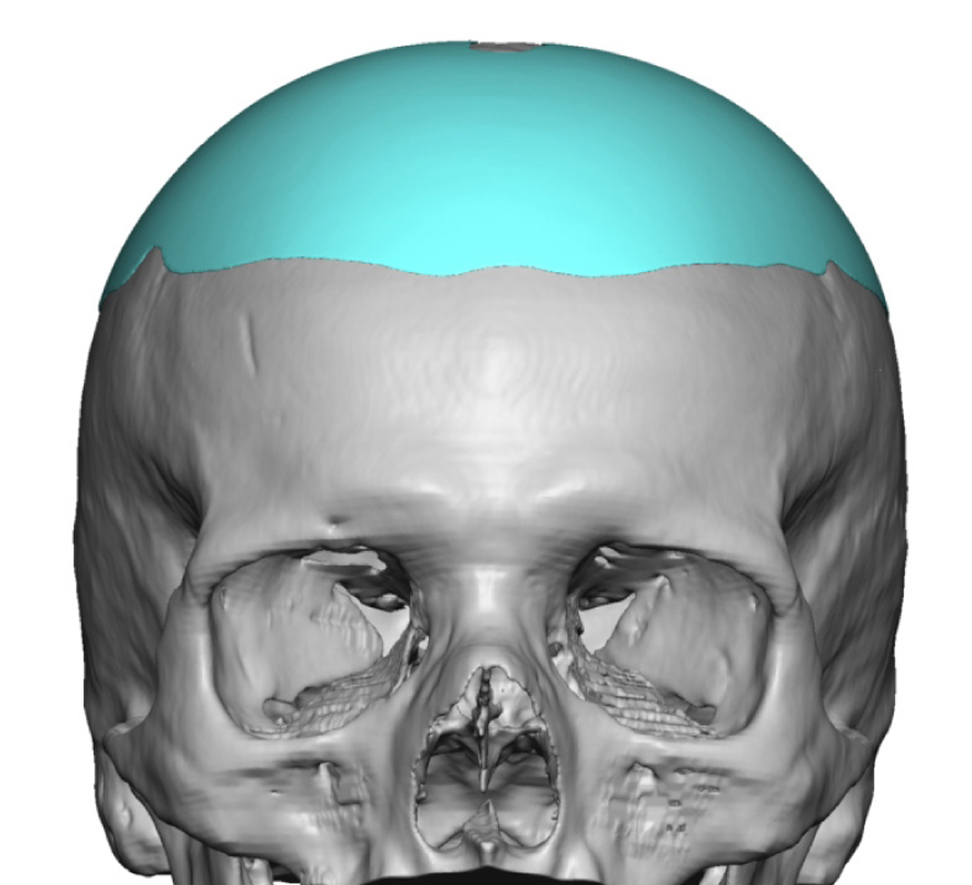

Patient 84

Desire for change of head shape from front view form an inverted V shape to a rounder and wider head shape.

Placement of custom extended forehead-temporal implants through incisions in the crease behind the ear. (he had a prior back of head skull implant which is green in the implant designs and which the head widening implants partially covered it)

Desire for change of head shape from front view form an inverted V shape to a rounder and wider head shape.

Placement of custom extended forehead-temporal implants through incisions in the crease behind the ear. (he had a prior back of head skull implant which is green in the implant designs and which the head widening implants partially covered it)